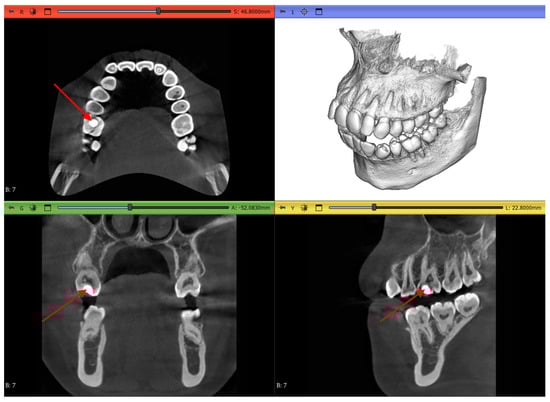

2.3.1. Volume Cropping

2.3.2. Histogram Adjustment